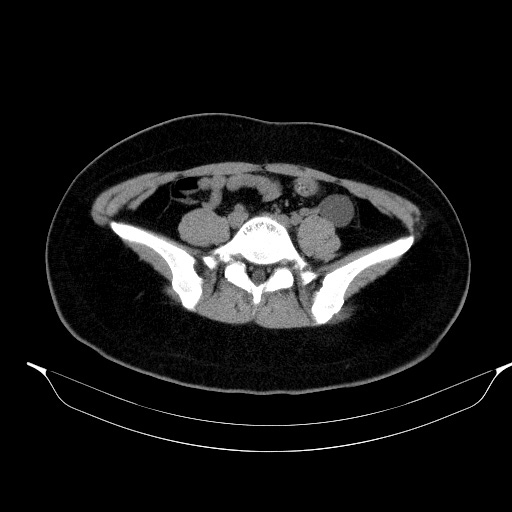

조영증강 전 영상에서 병변의 위쪽과 아랫쪽의 감쇄도(attenuation)가 다름을 알 수 있습니다.

초음파영상에서 보였던 낭성병변은 CT에서는 하행결장과 뚜렷하게 떨어져 있었기에 duplication cyst는 배제할 수 있으며, lymphangitic cyst의 가능성도 떨어져 보입니다. 해당 병변은 Lt. adnexal region에 있는 병변으로 생각됩니다.

조영증강이 되지 않고, 초음파에서 무에코음영을 보인 부분은 단순낭종으로 생각할 수 있습니다. 초음파영상에서 약간의 에코음영이 보였던 부위는 조영증강이 되지 않은 대신 균일한 연부조직음영을 보여 낭종 내에 출혈 가능성을 배제하기 어려웠습니다.